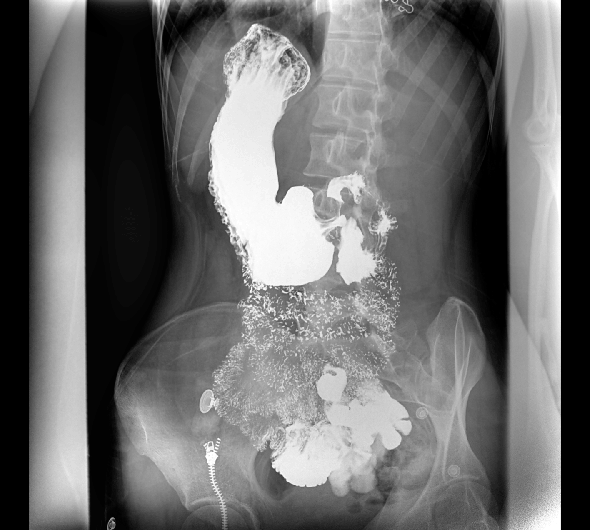

原厂优质影像链,搭载直接生长式碘化铯非晶硅平板,带来更加清晰锐利的图像效果。